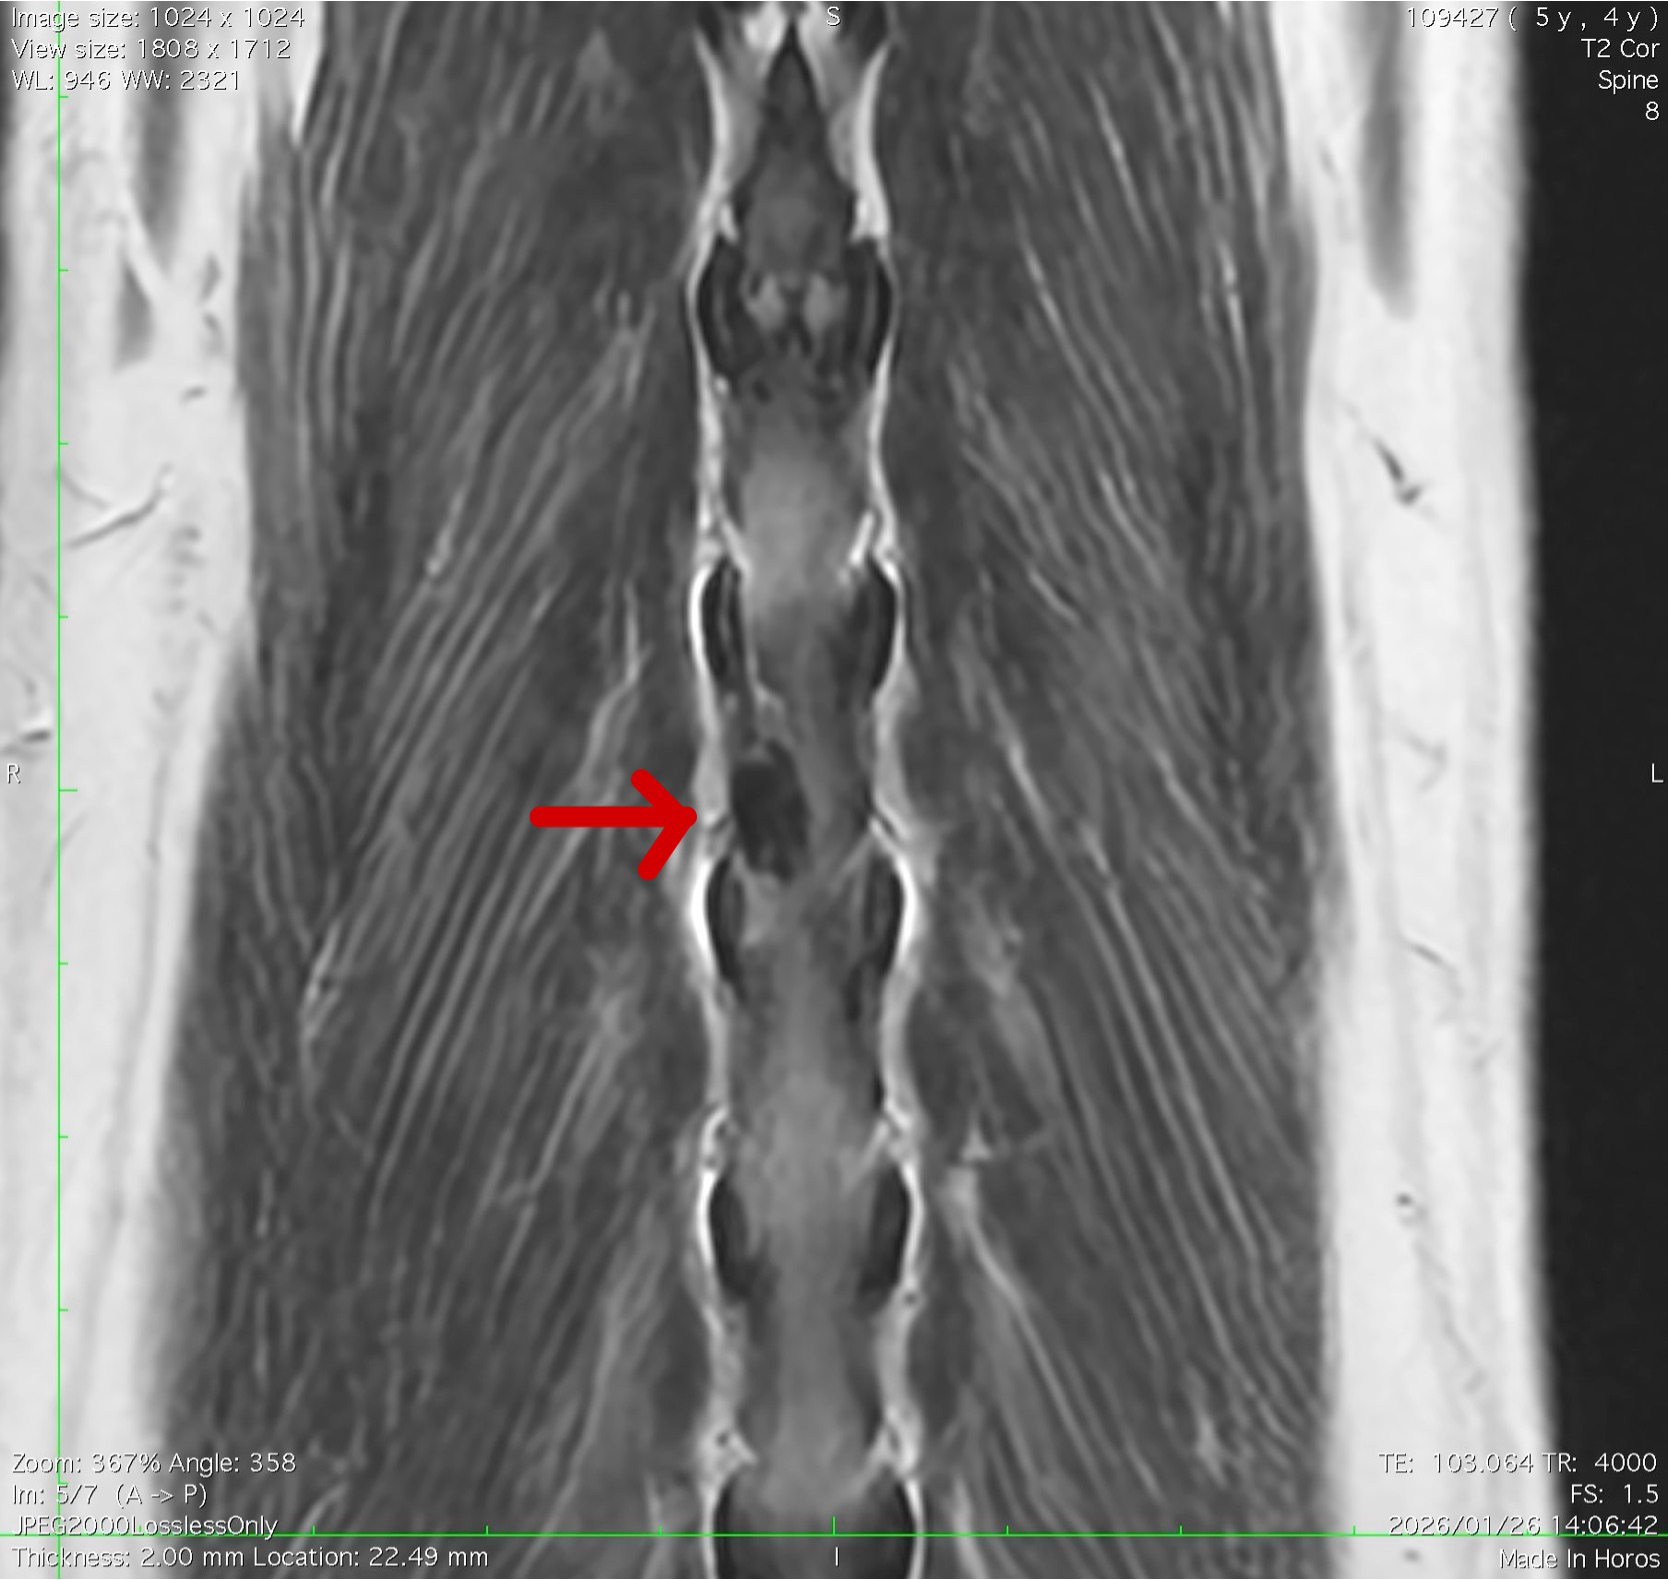

MRI画像 Cornal断面

椎間板が脊髄に腹側から圧迫している